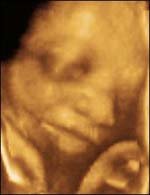

Baby has had a face that resembles his father and mother. Baby's brain develops more rapidly. At this time the baby's brain also have started to coordinate, among others, the baby is sucking his thumb and was able to swallow. Although the baby's bones have hardened, but the muscles of the baby has not really united. Your baby may take a deep breath though his breathing was still in the water. If the baby is a boy then the baby has started down the testis from the abdomen into the scrotum. Weight infants 1800-1900 grams, with a height of about 43-45 cm.